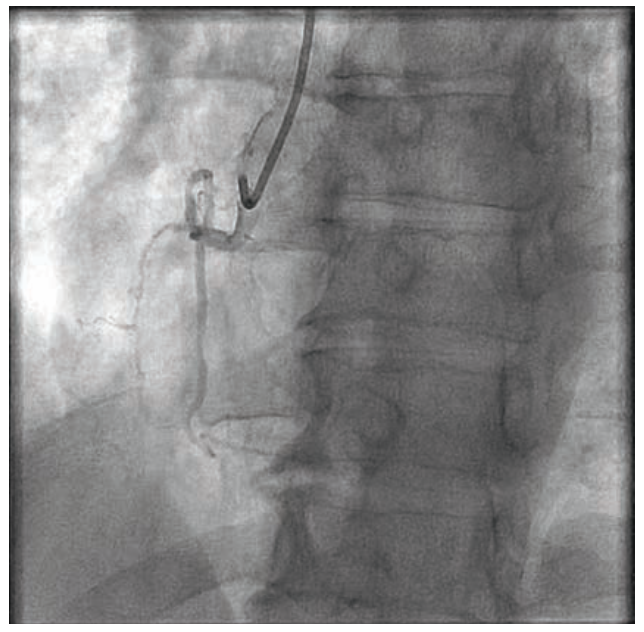

A 57-year-old man was admitted to the hospital for unstable angina. He had undergone an electrocardiogram showing possible old inferior myocardial infarction and echo abnormalities concordant with inferior wall motion abnormalities. A Lexiscan Cardiolite scan showed reversible inferior ischemia. Cardiac catheterization did not show any hemodynamically significant left coronary artery disease. There was a right coronary artery (RCA) chronic total occlusion (CTO) (Figure 1). There were collaterals to the distal RCA via the left anterior descending and circumflex coronary arteries. Left ventriculography showed a left ventricular ejection fraction of 40% to 45% with inferior hypokinesia and inferobasilar hypokinesia. There was no mitral insufficiency.

Owing to the patient’s anginal symptoms and ischemia inferiorly on the Cardiolite imaging, it was elected to open the RCA CTO. An Amplatz Left 1 6 French (Fr) guiding catheter was placed into the anterior takeoff RCA. A Turnpike Spiral microcatheter (Teleflex) with an .014-inch Minamo wire (Asahi Intecc) was initially chosen but could not traverse the stenosis, so the wire was replaced with an .014-inch Sion black wire (Asahi Intecc). This wire appeared to be extraluminal, and was removed and replaced with an .014-inch Mongo wire (Asahi) in the distal vessel, which appeared to track in the true lumen (Figure 2). A 6 Fr GuideLiner (Teleflex) was placed, but in trying to ascertain distal wire position with an injection into the GuideLiner, the vessel appeared to be dissected (Figure 3). We could see the main channel distally, and therefore took a new Minamo 300 wire and placed it into the true lumen. The Mongo wire was removed. However, the Minamo wire would not traverse into the distal vessel, so it was changed for an .014-inch Choice PT Floppy wire (Boston Scientific), which was successful in going distally. We placed a Sasuke dual lumen 145 microcatheter (Asahi Intecc), removed the Choice PT wire, and placed a Balance Middle Weight (BMW) Universal 300 wire (Abbott Vascular). A GuideLiner had been used for support and we attempted to place a Synergy 3.5 mm x 48 mm stent (Boston Scientific). However, the stent would not go forward. It was removed and found to be intact on inspection. The stent was replaced with a 3.0 mm x 30 mm Monorail Emerge balloon (Boston Scientific) for further dilatation of the RCA to 6 atmospheres (atm) for overlapping 15-second inflations. A third inflation of 12 atm for 35 seconds was performed and the balloon was removed. A 3.0 mm x 38 mm Synergy drug-eluting stent (Boston Scientific) was not able to be placed adequately distally, and was removed, inspected, and found to be intact. It appeared that the GuideLiner might be preventing some forward motion of the stent and it too was removed. There was, on angiography, a flow abnormality consistent with a small branch wire perfusion abnormality. There was no clear-cut staining. An echo showed no evidence of pericardial fluid and no tamponade physiology. It was felt that this should be addressed and so a 1.5 mm x 12 mm Takeru balloon (Terumo) was inflated to 6 atm for 20 seconds, though this did not resolve the flow abnormality. Ultimately, a 2.5 mm x 15 mm PK Papyrus covered stent (Biotronik) was delivered to the site of flow abnormality and deployed to 6 atm for 60 seconds. Angiography after balloon deflation showed no further flow into the branch (Figure 4).